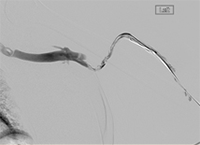

xray of occlusive thrombus extending into the iliac vein.

Occlusive thrombus extending into the iliac vein

xray of femoral vein pre-treatment.

Femoral vein pre-treatment